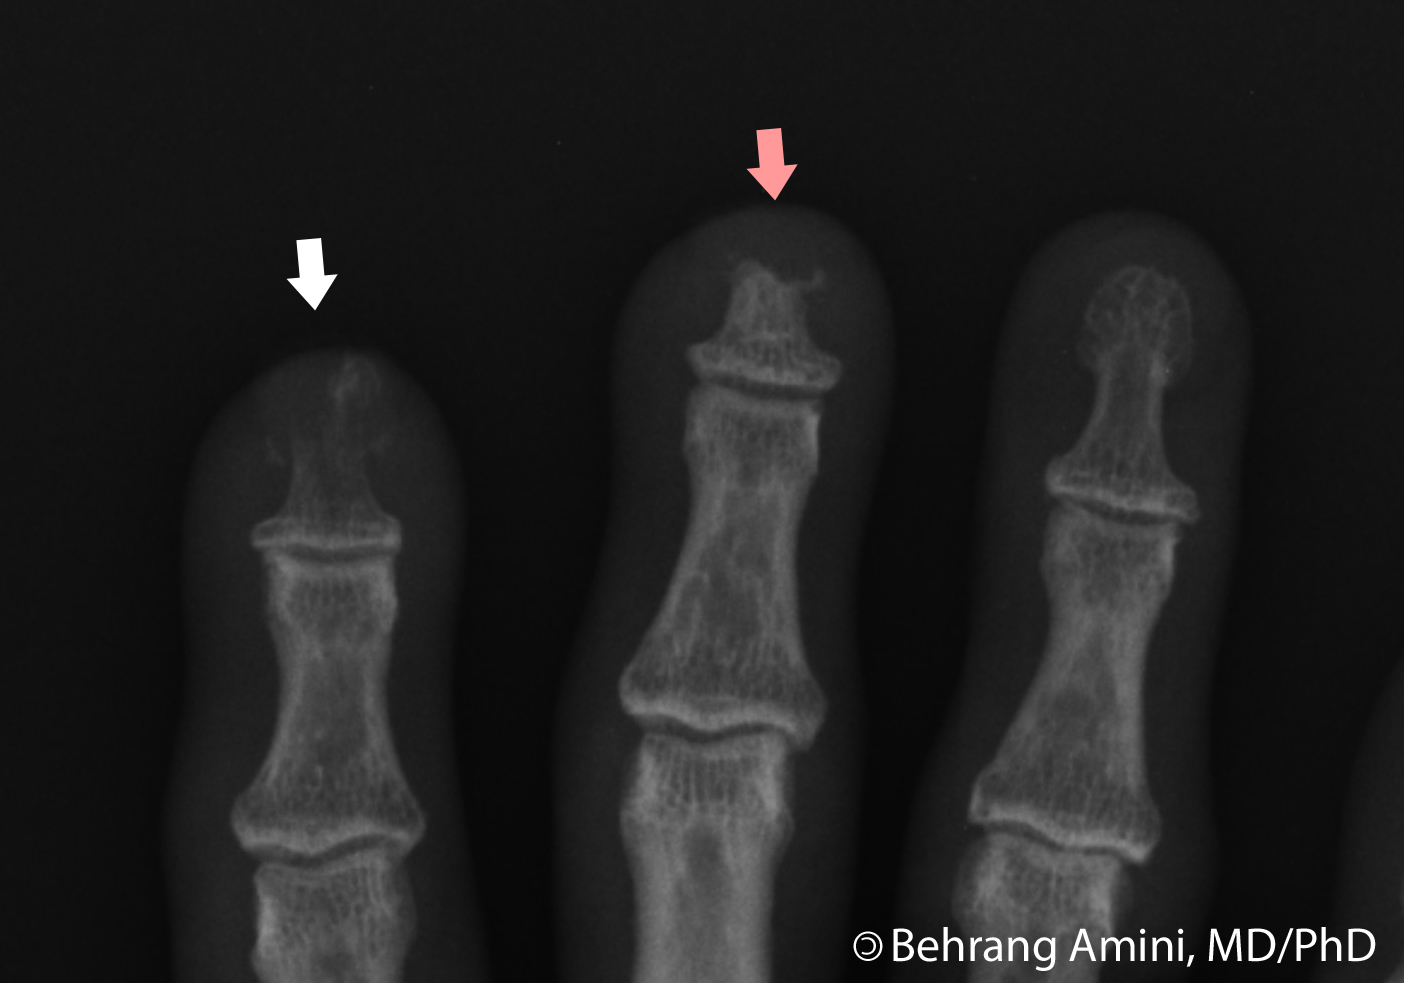

Рентгеновские снимки остеомиелита большого пальца стопы